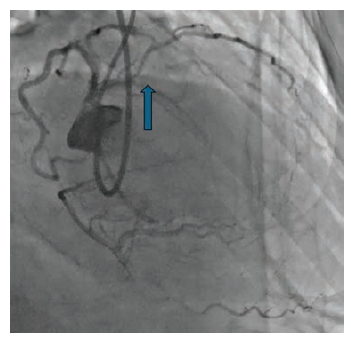

Rotational atherectomy was performed using a 2.0 mm burr. Subsequent angiography showed an excellent result post atherectomy (Figure 3A). However, OCT intravascular imaging showed persistent presence of circumferential calcium greater than 270 degrees and 0.5 mm in depth, with a minimal lumen area (MLA) of 7.06 mm2 (Figure 3B).